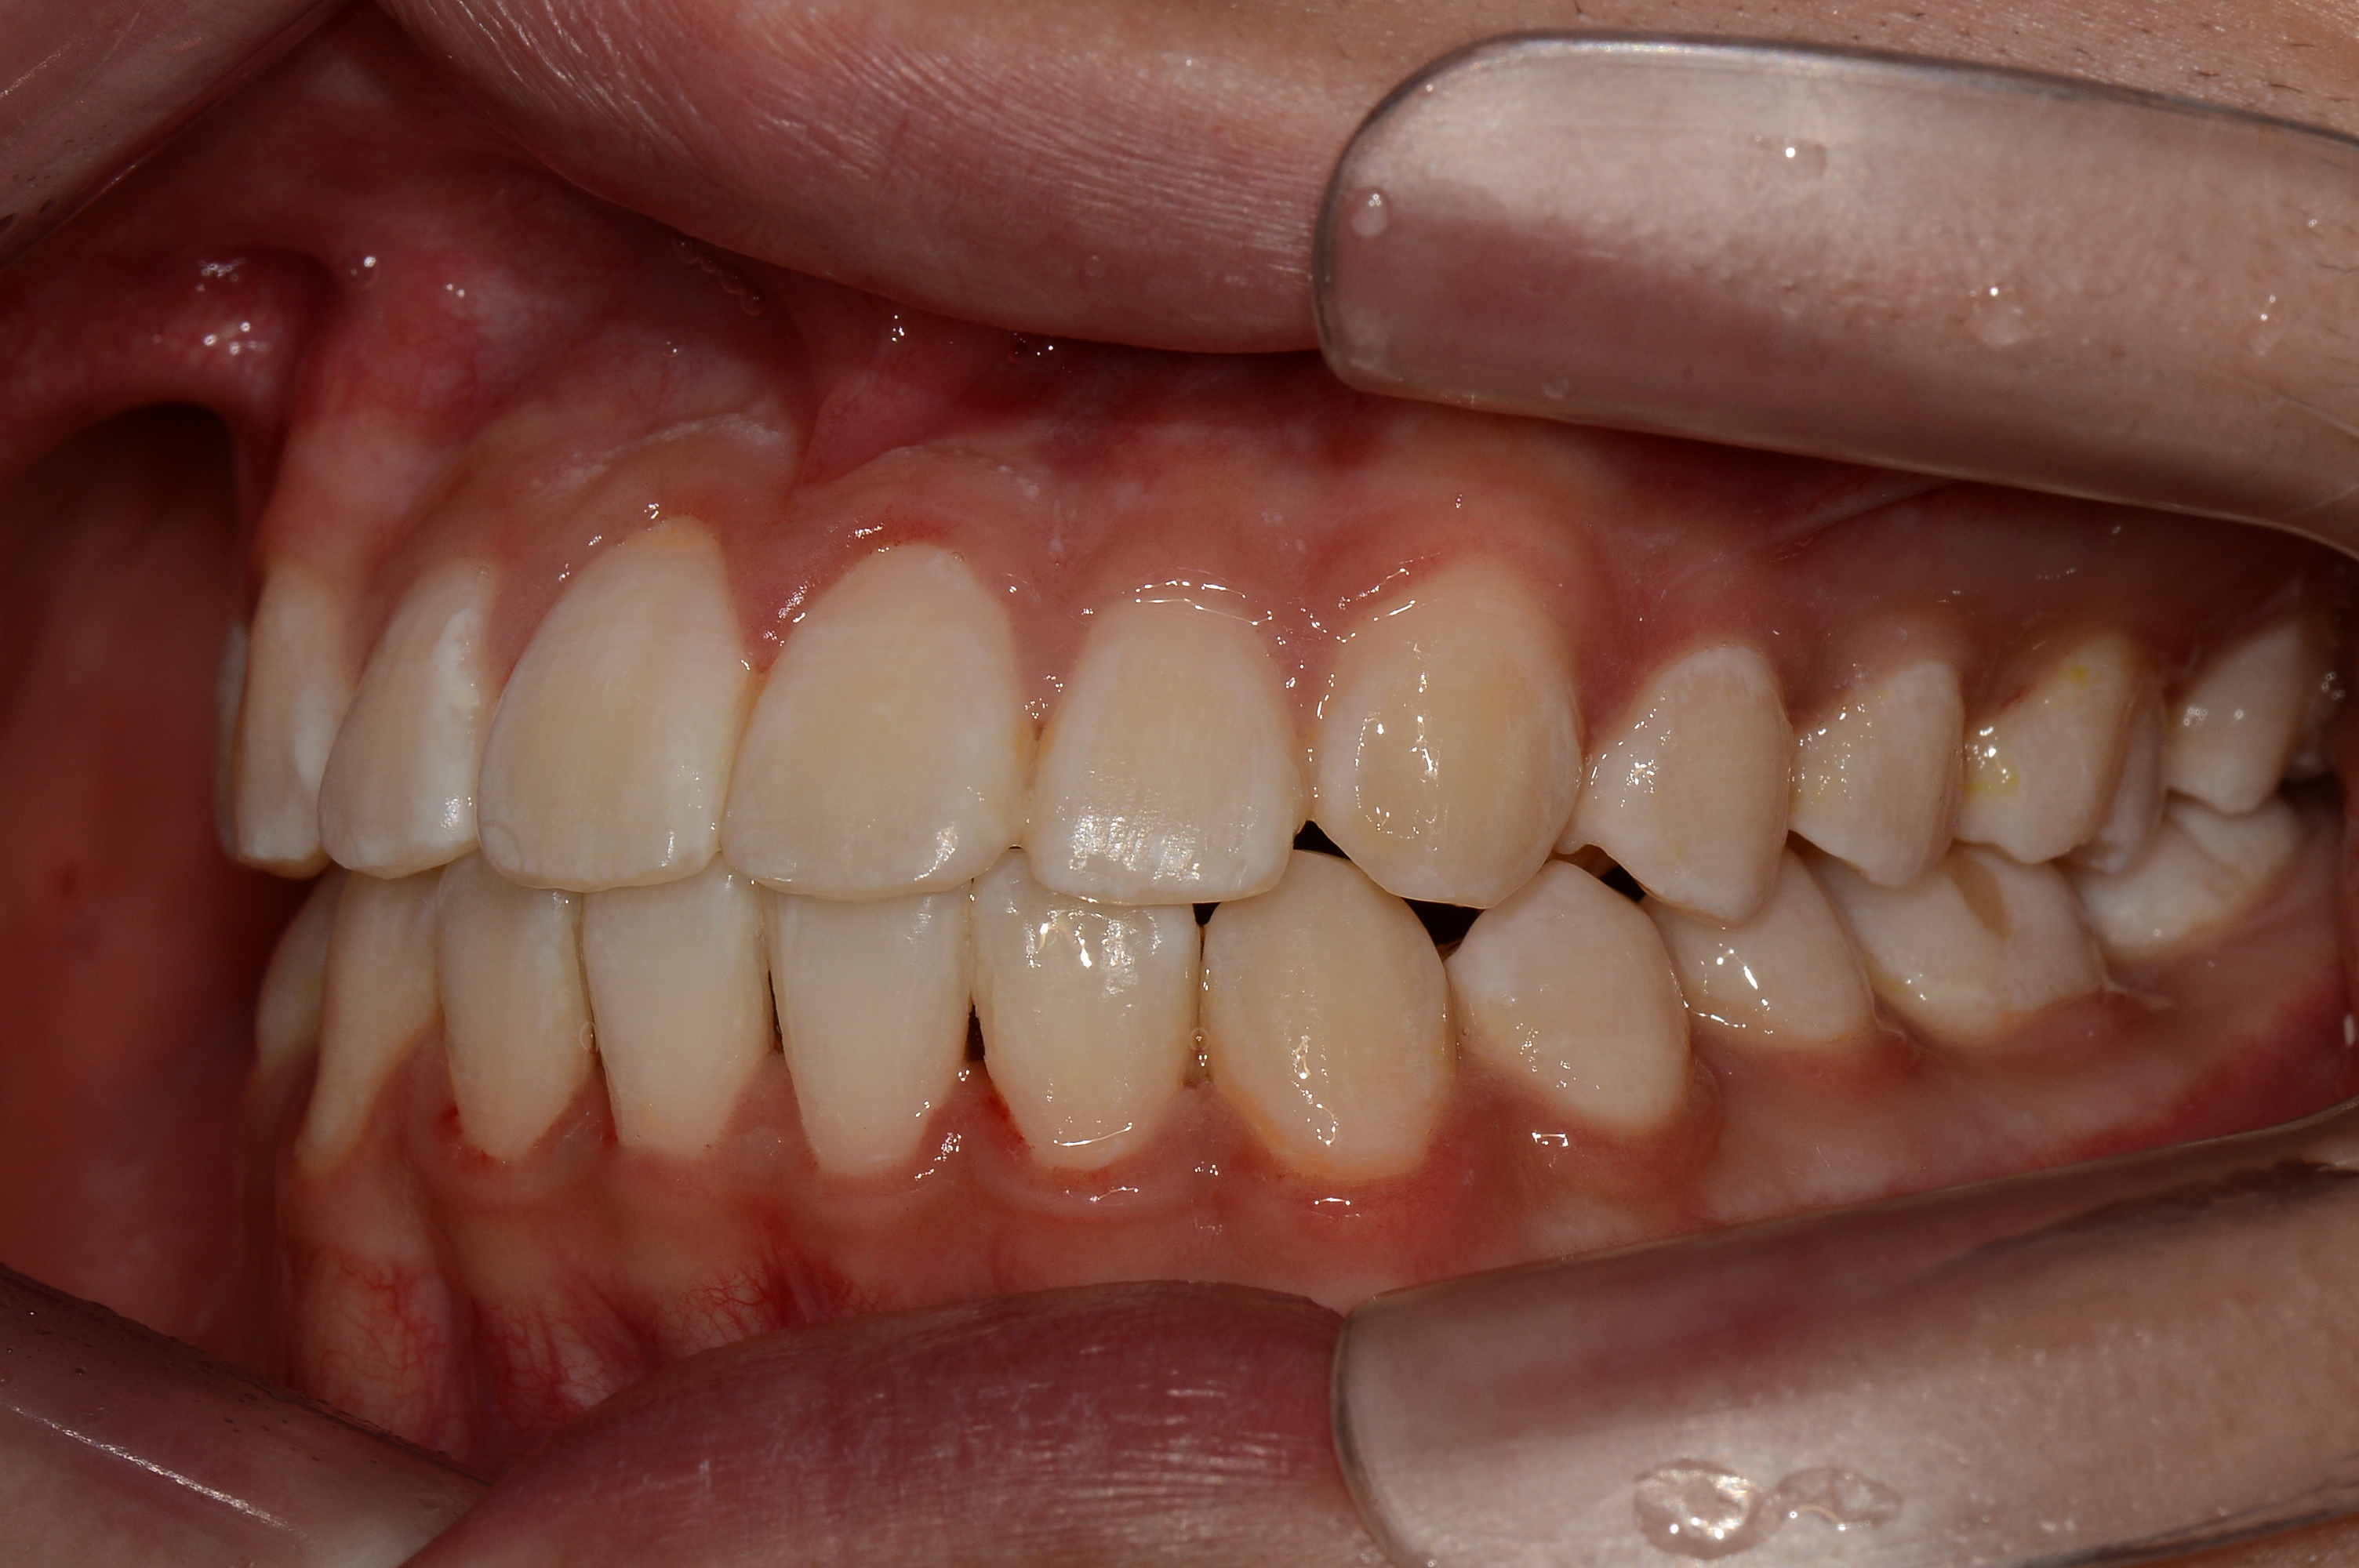

치료 후 사진입니다.